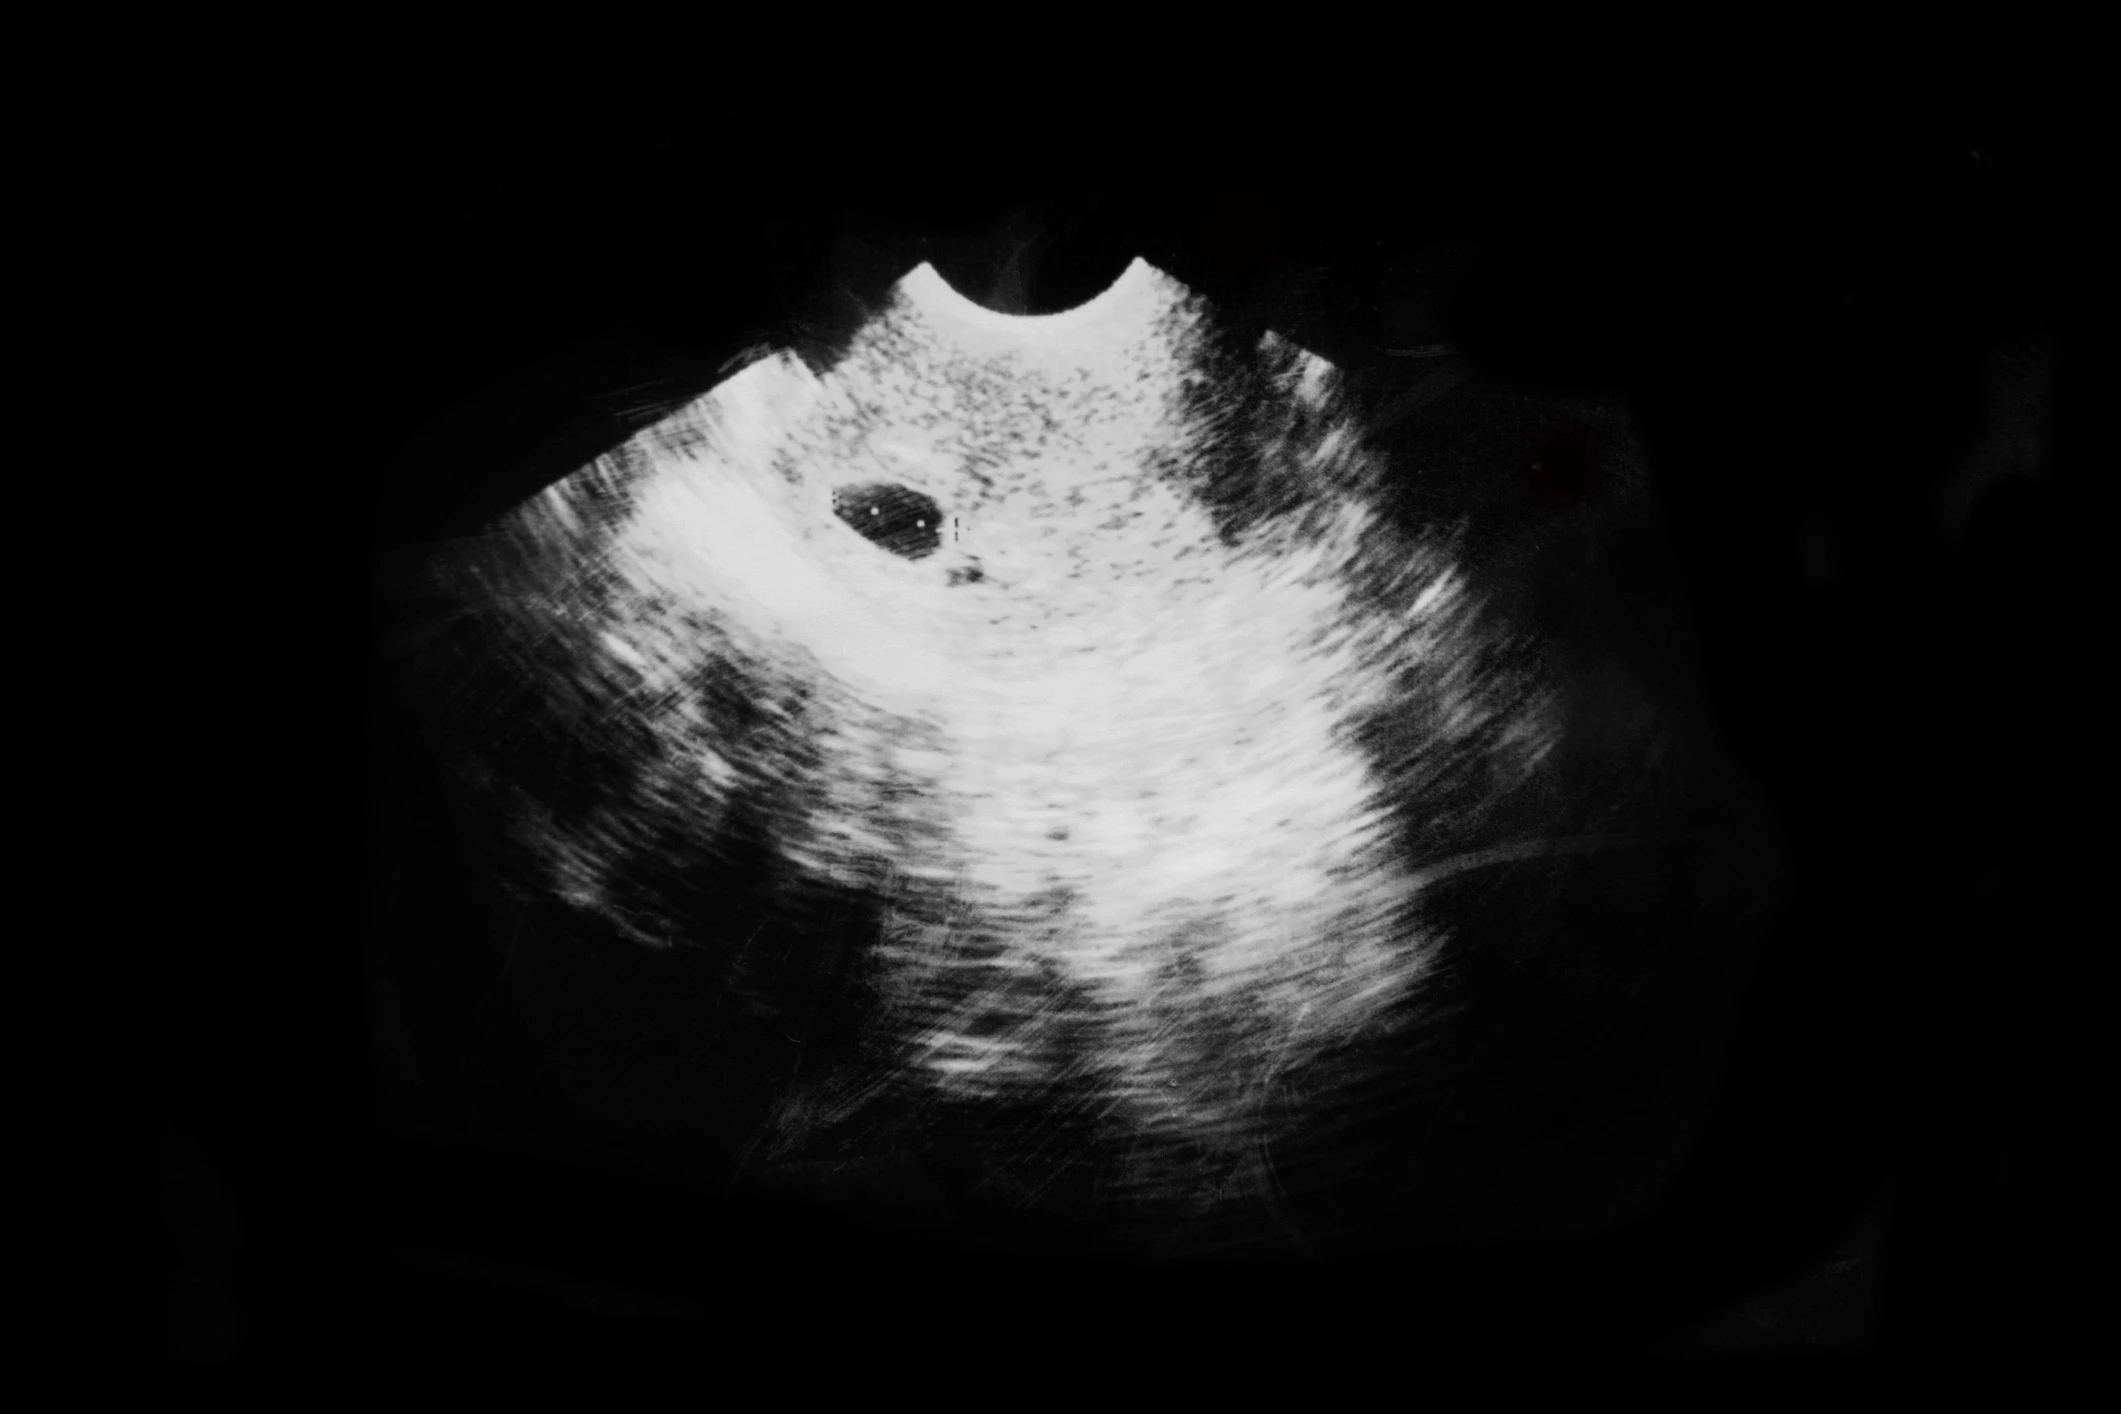

A negyedik hét végére babádat már megilleti az embrió elnevezés. Az embrionikus sejtek elképesztő tempóban nőnek, ráadásul minden sejt napjában osztódik is. A terhesség negyedik hetére a fejlődő baba már kb. 1 mm hosszú, és leginkább egy apró ebihalra emlékeztet. Erősen a méhfalhoz tapad, és hormonokat juttat a te véráramodba. Megkezdődik a placenta (méhlepény) kialakulása, de még rengeteg fantasztikus és izgalmas változás előtt állsz.